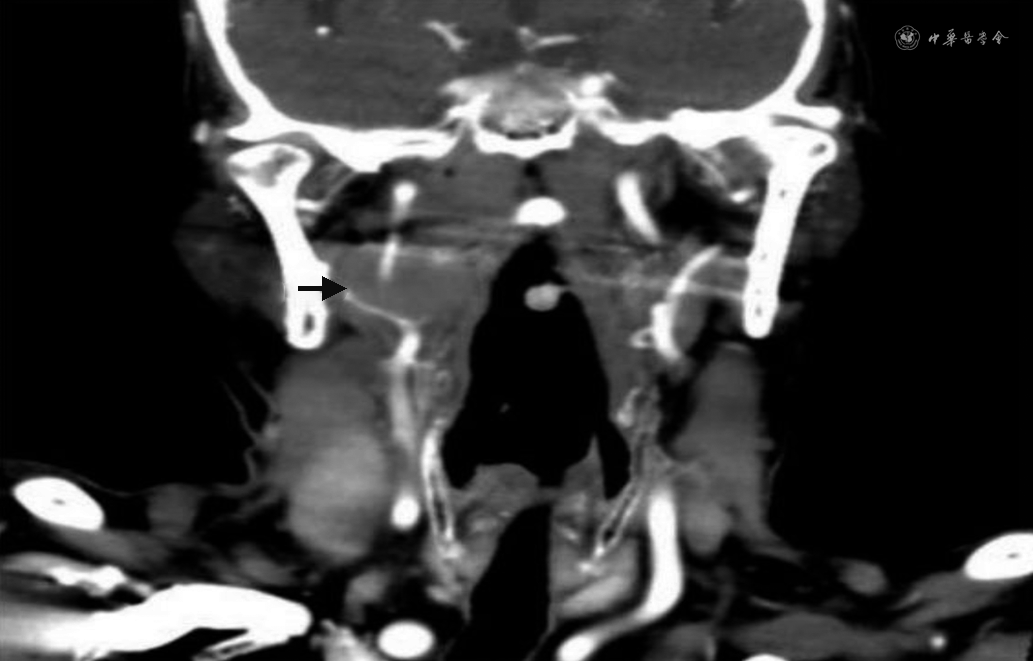

完善24 h动态心电图示:心搏总数77 945次,其中室性心搏4次,室上性心搏53次。心率40~100次,心动过缓心搏26 140次(33.5%),最长RR间期13.37 s,窦性心动过缓伴不齐;夜间显著窦性心动过缓伴不齐;心室长间期>2 s共987次,最长达13.37 s;心率变异性分析:全部窦性心搏RR间期的标准差(SDNN)、RR间期平均值标准差(SDANN)、相邻RR间期差值(rMSSD)升高,PNN 50%正常。室性节律4个,室上性节律51个。心脏彩超示:左室壁运动轻度不协调。颈部CT增强示:右侧咽旁及右侧颈部见多发肿大淋巴结影,部分融合成团,大者位于右颈动脉鞘区,大小4.4 cm×2.0 cm(图1),并包绕推移压迫周围动静脉。颈部CT血管造影(CTA)示:右侧颈内动脉颈段狭窄(图2),考虑肿瘤压迫所致。

本案例中的患者既往无晕厥史,心电图及心脏彩超检查均未提示器质性心脏病。入院后目击患者晕厥发作,表现为无明显诱因突发意识丧失,呼之不应,伴全身大汗,皮肤湿冷,心电监护提示心率及血压下降。考虑患者既往淋巴瘤病史,颈部存在肿大淋巴结,故予进一步完善颈部CT增强及颈部CTA检查,检查结果提示颈动脉窦受压及颈内动脉狭窄。结合患者晕厥发作史及辅助检查,考虑患者晕厥系颈动脉窦综合征(CSS)引起的可能性大。